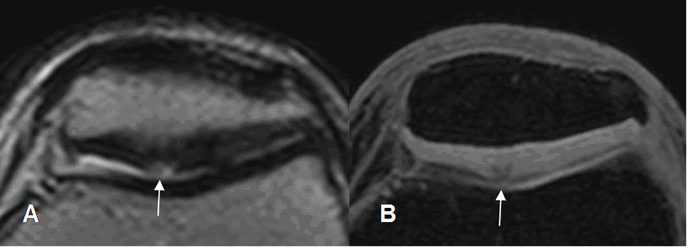

Fig 167. Condromalacia patelar grado 2.

A y B: RM axial en 3D T1 STIR. Adelgazamiento del cartílago articular menor del 50%.